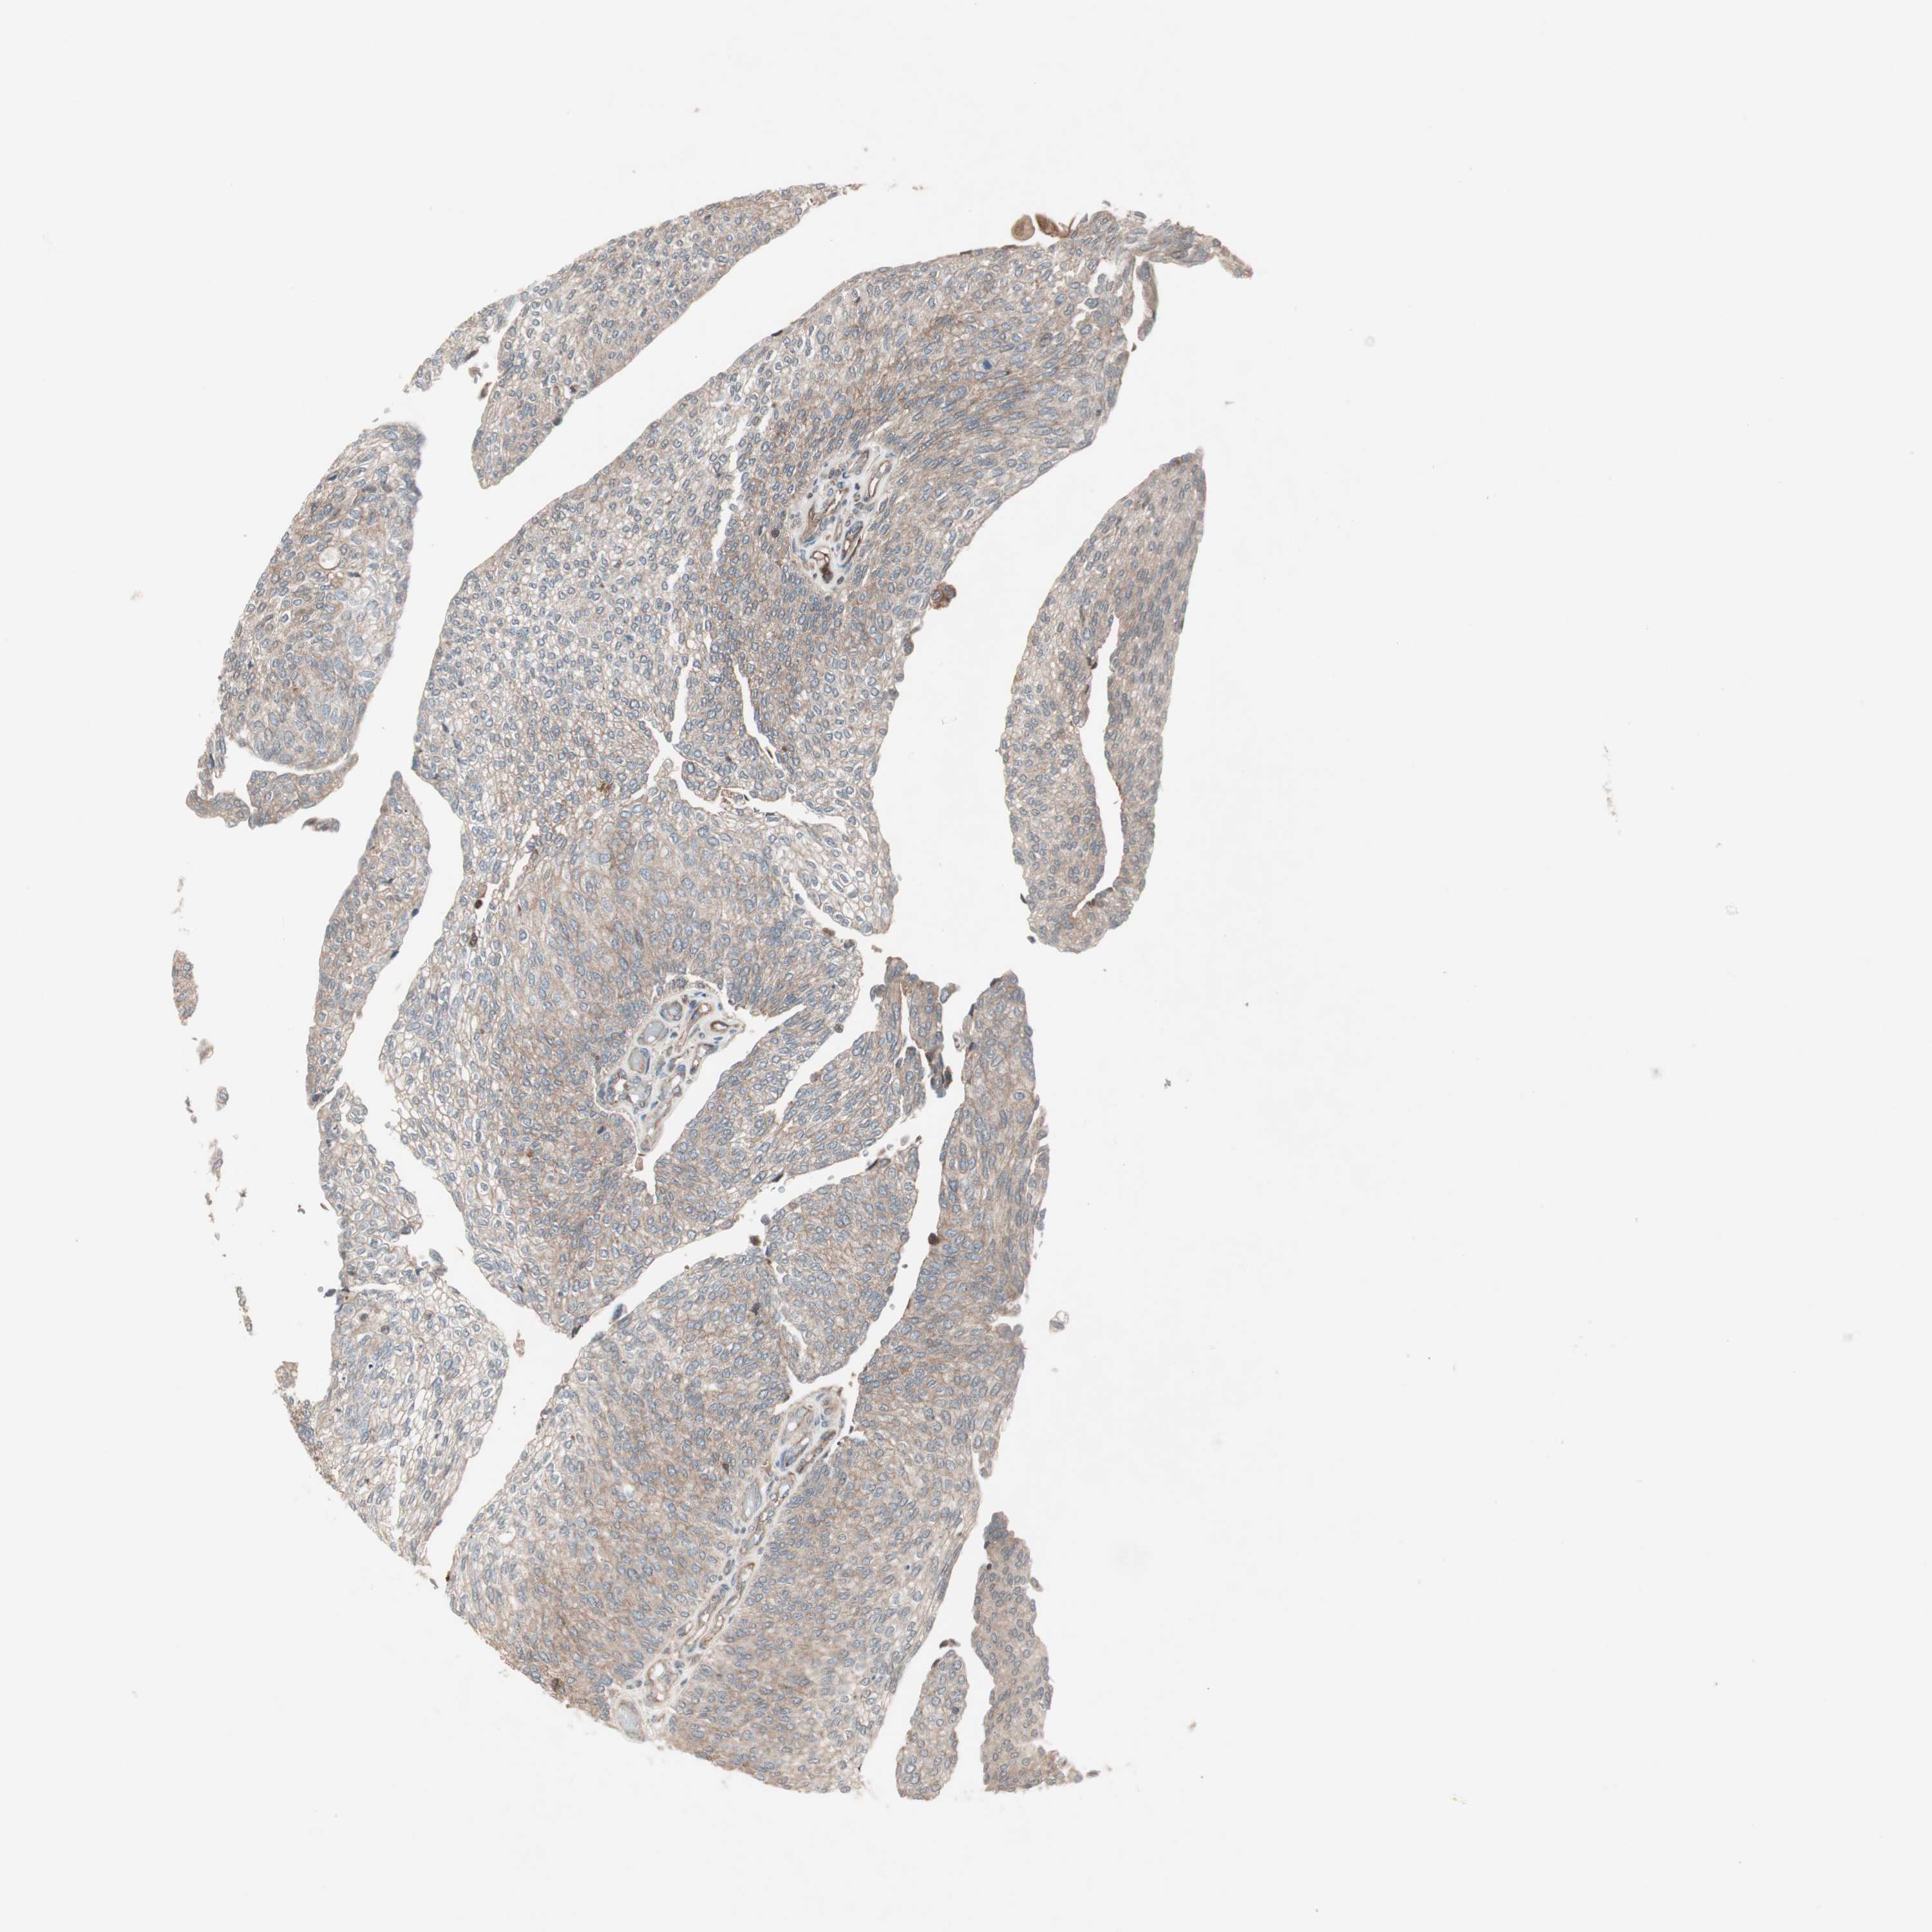

UROTHELIAL CANCER - Protein expressioni

A mouse-over function shows sample information and annotation data. Click on an image to view it in a full screen mode. Samples can be filtered based on level of antibody staining by selecting one or several of the following categories: high, medium, low and not detected. The assay and annotation is described here.

Note that samples used for immunohistochemistry by the Human Protein Atlas do not correspond to samples in the TCGA dataset.

Antibody stainingi

Antibody staining in the annotated cell types in the current human tissue is reported as not detected, low, medium, or high, based on conventional immunohistochemistry profiling in selected tissues. This score is based on the combination of the staining intensity and fraction of stained cells.

Each image is clickable and will lead to virtual microscopy that enables deeper exploration of all samples and also displays staining intensity scores, fraction scores and subcellular localization as well as patient and tissue information for each sample.

Antibody HPA005575

Antibody CAB020842

Urothelial carcinoma, Low grade

Urothelial carcinoma, High grade